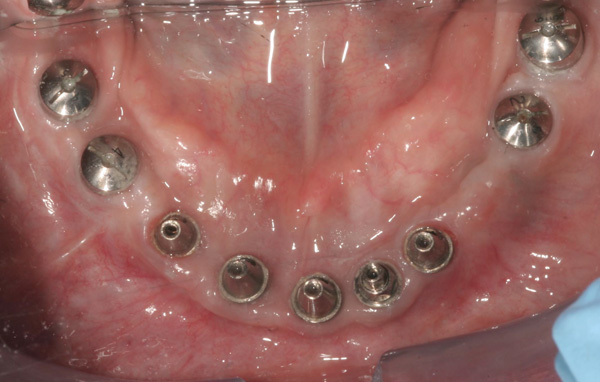

Background: In this case, the patient had a failing mandibular and maxillary dentition due to caries secondary to radiation-induced xerostomia. The patient had had a radical neck dissection to remove a squamous cell carcinoma of the throat 9 years prior to his prosthodontic consultation with the authors. The patient reported a history of radiation therapy following surgery, but did not have a shielding stent. A staged approach was used so as to avoid removable prosthetics on his severely dry soft tissues. He chose to treat his mandibular issues first. Figure 9 shows healing abutments next to the temporarily retained natural teeth, and Figure 10 shows the first-stage custom abutments inserted with relatively good gingival contour and no recession. Recession was clearly seen around all first-stage abutments following adjacent extractions and second-stage implant placement (Figure 11).

Figure 9 Healing abutments.

Figure 9

Figure 10 First-stage custom abutments.

Figure 10

Figure 11 Recession evident around first-stage abutments following adjacent extractions and second-stage implant placement.

Figure 11